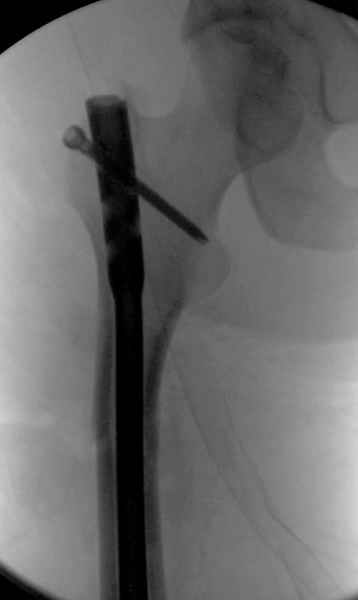

Второй случай тоже репозиция из малого доступа, больному 19 лет, множественные огнестрельные повреждениия конечностей, живота и черепа, правая конечность холодная, без пульсации. Ортопедический диагноз: огнестрельный перелом правого бедра. При срочной ангиографии повреждения сосудов не подтвердилось, конечность из-за ургентности состояния больного зафиксирована временным наружным фиксатором и больной оставлен на операционном столе для срочной лапаротомии хирургической службой.

Больной долго оставался нестабильным, только на 14 день удалось заменить на антеградный интромедуллярный штифт TFN (trochanteric femoral nail) SmithNephew. После неудачной попытки закрытой репозиции, несмотря на использование "joystick", проксимальный стержень от

наружного фиксатора, (перелом начал срастаться) репозицию провели из малого доступа, затем остальные этапы операции.

Случай был представлен из-за того, что больного оперировали после наружной фиксации и был риск инфекцирования через места проведения стержней (на снимках), прошло больше 3 месяцев, выписан из амбулаторной службы из-за отсутсвия надобности дальнейшего наблюдения.

Другие случаи: применение Synthes TTFN (trochanteric titanium femoral nail) и Blade Plate (угловая пластина), так что много различных вариантов фиксации подобных переломов.